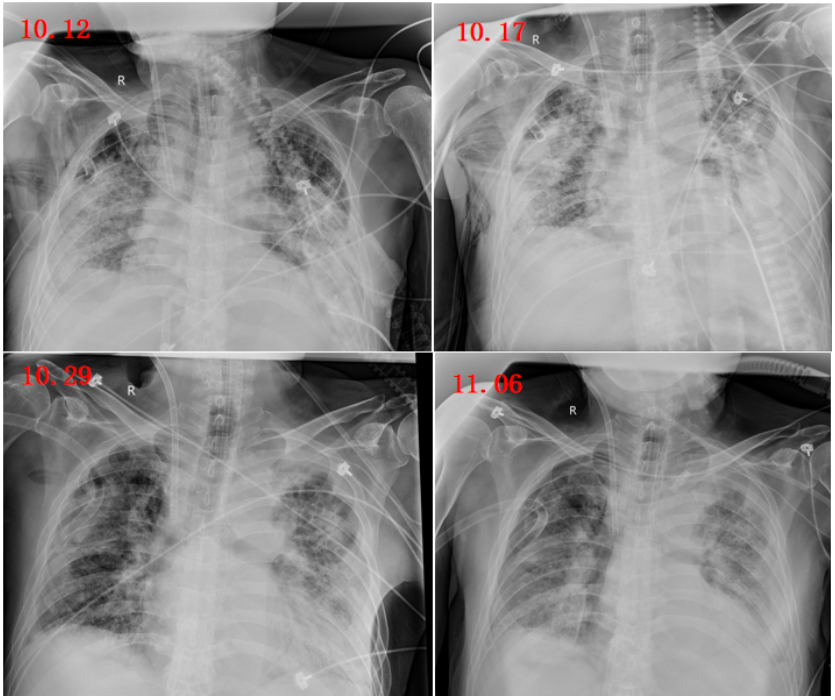

影像变化趋势

图7所示为患者ECMO(10月10日-11月10日)治疗期间影像学检查结果。患者氧合状况明显改善,肺部阴影有所吸收,但仍可见部分渗出影。鉴于影像学改变往往具有一定滞后性,因此拟行脱机试验。

图片

图7  患者影像学变化情况

由于患者住院时间较长,肌肉萎缩,呼吸肌力丧失,于1月15日行气管切开,镇静镇痛逐步减量,降低呼吸支持力度,同时采取措施促进胃肠功能恢复,并积极进行康复锻炼。12月7日复查胸片,可见肺部阴影进一步吸收(图9)

图9  复查胸片(2023-12-07)